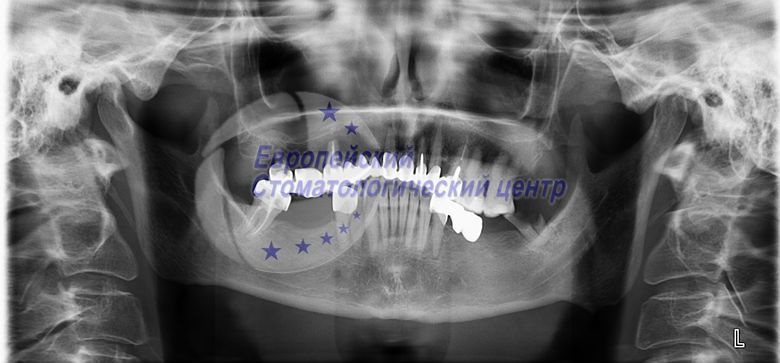

ОЗУ до операції